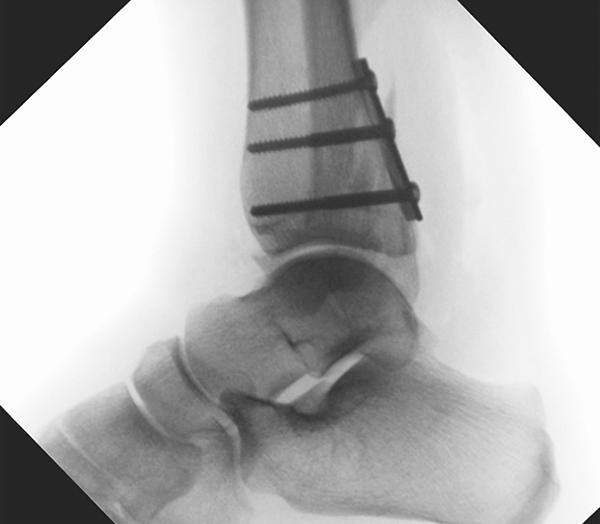

Die Versorgung von AO 44-B Frakturen erfolgt über einen längsverlaufenden lateralen Zugang. In der Regel gelingt eine suffiziente Stabilisierung mittels interfragmentärer Zugschraube (bei langem Frakturverlauf ggf. 2 Zugschrauben) und einer zusätzlichen Neutralisationsplatte (Abbildung 9 & 10).

Frakturen vom Typ AO 44-C werden in der Regel mittels interfragmentärer Zugschraube und Neutralisations-Plattenosteosynthese versorgt. Die Versorgung von Frakturen mit metaphysärer Trümmerzone (AO 44-C2) ist mitunter anspruchsvoll. Entscheidend ist die Wiederherstellung der korrekten Länge und Rotation der Fibula. Die Verwendung von winkelstabilen Implantaten bietet hier eine höhere Stabilität. Bei Typ C Verletzungen liegt definitionsgemäß eine Syndesmoseninsuffizienz vor, die entsprechend versorgt wird (siehe Abschnitt Syndesmoseninsuffizienz). Bei hohen Fibulafrakturen (AO 44-C3, Maisonneuve-Frakturen) steht die Versorgung der Syndesmoseninstabilität im Vordergrund. Eine zusätzliche Versorgung der proximalen Fibulafraktur ist nicht erforderlich.